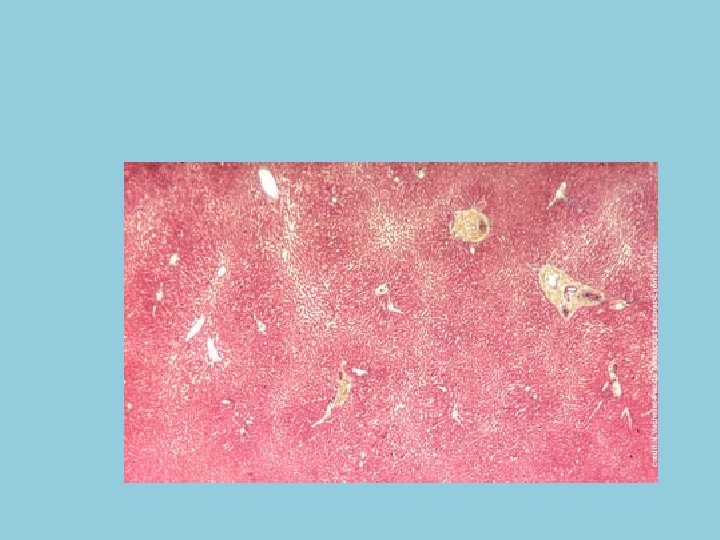

• La structure élémentaire du tissu hépatique est le lobule hépatique, qui est fait d'un groupement de cellules hépatiques (hépatocytes) centré sur une veinule qui est une branche initiale de la veine sus-hépatique; le lobule hépatique est entouré d'espaces portes, où sont groupées les branches de l'artère hépatique, de la veine porte et des canaux biliaires. Le sang circule à travers les hépatocytes des espaces portes vers les veines centrolobulaires.

Détails du tissu hépatique • l'espace de Kiernan contient une artériole (issue de l'artère hépatique) à lumière arrondie, étroite, et à paroi épaisse composée d'un endothélium et de quelques fibres musculaires lisses, une veinule (issue de la veine porte) à lumière large contenant des hématies et à paroi mince, une fente lymphatique à paroi extrêmement fine, et un canal biliaire à lumière arrondie et à paroi épithéliale formée d'un épithélium prismatique simple

• les hépatocytes (organisés en travées anastomosées) sont des cellules polygonales de grande taille au noyau central, rond, volumineux et au cytoplasme éosinophile granuleux , certains hépatocytes sont binuclées • les capillaires sinusoïdes n'ont pas de membrane basale; la paroi endothéliale est discontinue et formée de deux types cellulaires : les cellules endothéliales et les cellules de Küpffer = cellules réticulaires bordantes ou macrophages bordants; les capillaires sinusoïdes assurent la circulation sanguine depuis les vaisseaux contenus dans les espaces portes (et les vaisseaux périlobulaires) jusqu'à la veine centrolobulaire; on dit que la circulation sanguine du lobule hépatique est centripète • les canalicules biliaires, mis en évidence par des techniques spéciales (injection d'encres, imprégnation de Gomori) se révèlent dépourvus de paroi propre; les membranes plasmiques d' hépatocytes voisins s'écartent en vis à vis pour former le petit canalicule biliaire fermé étroitement par des complexes de jonction; le canalicule biliaire véhicule la bile de façon centrifuge en direction des espaces de Kiernan; à leur proximité, il se continue par le passage de Hering pour aboutir au canal biliaire

CAPILLAIRES SINUSOÏDES (UCLB - N. Vacheret). Notons l'existence d'un espace entre les hépatocytes et le capillaire; dans cet espace appelé espace de Disse, des fibres de réticuline soutiennent le parenchyme intralobulaire; la paroi endothéliale est discontinue et une cellule de Küpffer est représentée; les canalicules biliaires coupés transversalement sont des petits "trous" blancs entre des hépatocytes voisins.